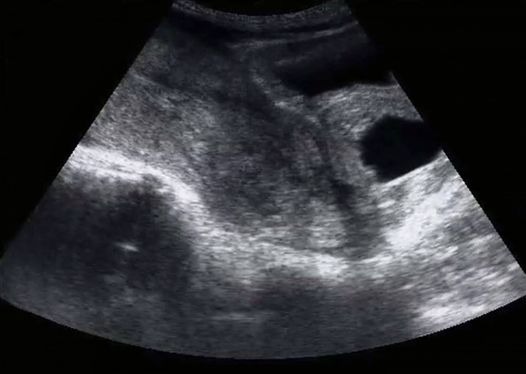

”Det var en dag som jag och min man hade väntat på i över ett år. Vi hade sett fram emot att se vår lilla bebis genom ultraljudet. Men det här var inte som bilderna jag hade sett på Facebook, som alla mina vänner hade delat. Någonting var fel.

Jag såg ingenting på skärmen eftersom min kropp var bara timmar från att förlora barnet. Ultraljudstekniken var tyst och jag visste bara att något var fel. Hon lämnade rummet och min man försäkrade mig att ”allt var bra.” Men det är inte vad en tjej som sett hundratals ultraljudsbilder och sökt Instagram efter hashtaggen ”8 veckor” för att se hur bebisen nu såg ut sa.